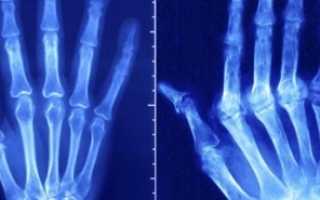

- Припухание суставных флангов указательного и среднего пальцев, лучезапястного сустава с признаками воспалительного процесса.

- Боль в симметрично пораженных суставах обеих рук (чаще в ночью и под утро).

- Деформация суставов стоп рядом с основанием пальцев. Сопровождается болезненными ощущениями при нажатии на пальцы ног.

- Воспалительный процесс в крупных суставах при прогрессировании болезни (плечи, локти, колени). Иногда воспаление начинается именно с крупных суставов, а в последствии переходит на кисти рук.

Наглядная информация про артрит